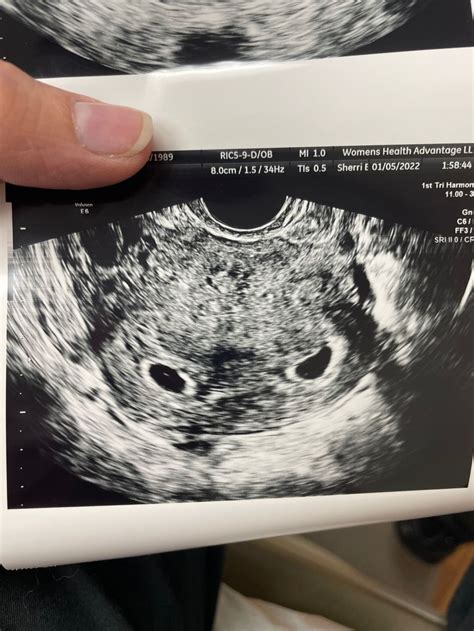

A 5 week sonogram is an ultrasound performed around the fifth week of pregnancy. At this stage, the embryo is still very small, typically measuring about 2-3 millimeters in length. The primary goal of this ultrasound is to confirm the presence of a gestational sac within the uterus, which indicates a viable pregnancy. Additionally, it helps to determine the location of the pregnancy, ruling out ectopic pregnancies, and provides an early estimate of the due date.

• Yolk Sac: Although it may not be visible at 5 weeks, the yolk sac is crucial for the embryoโ€™s early development and nutrition.

• Gestational Sac with Yolk Sac: This is a positive sign, indicating that the pregnancy is progressing normally.

8-10 Weeks Check for fetal heartbeat, measure crown-rump length Fetal heartbeat, embryo measurements